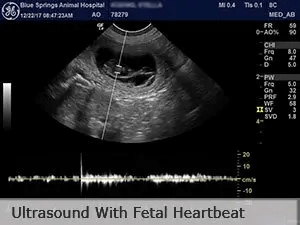

- Pregnancy can be confirmed by a veterinarian at 25-30 days by palpation and an ultrasound exam. Ultrasound allows visualization of the heartbeats to confirm live puppies.

- Pregnancy diagnosis with ultrasound of puppies and visualization of the fetal heartbeat

The following video during an ultrasound pregnancy diagnosis demonstrates fetal heartbeats with color flow doppler: